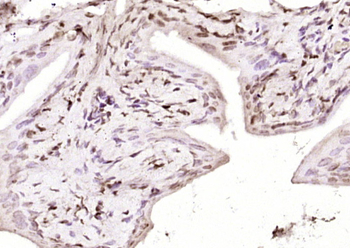

100 μl, 200 μl, 50 μl - LATS2 Rabbit Polyclonal Antibody [orb6306]Featured

IF, IHC-Fr, IHC-P, WB

Human, Mouse, Rat

Bovine, Canine, Equine, Gallus, Rabbit

Rabbit

Polyclonal

Unconjugated

100 μl, 200 μl, 50 μl - Featured